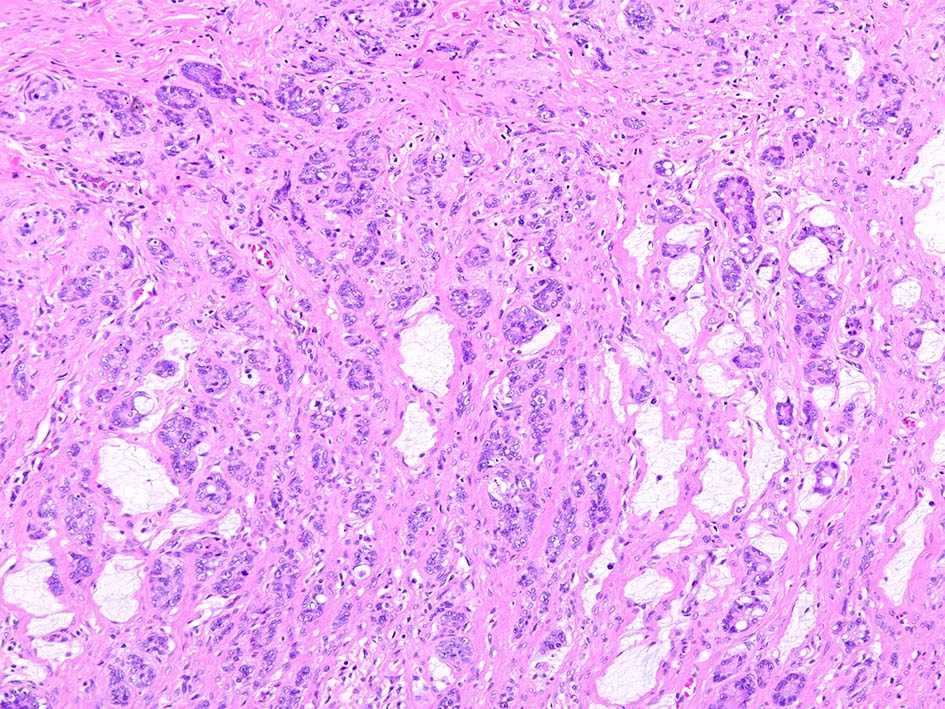

組織所見